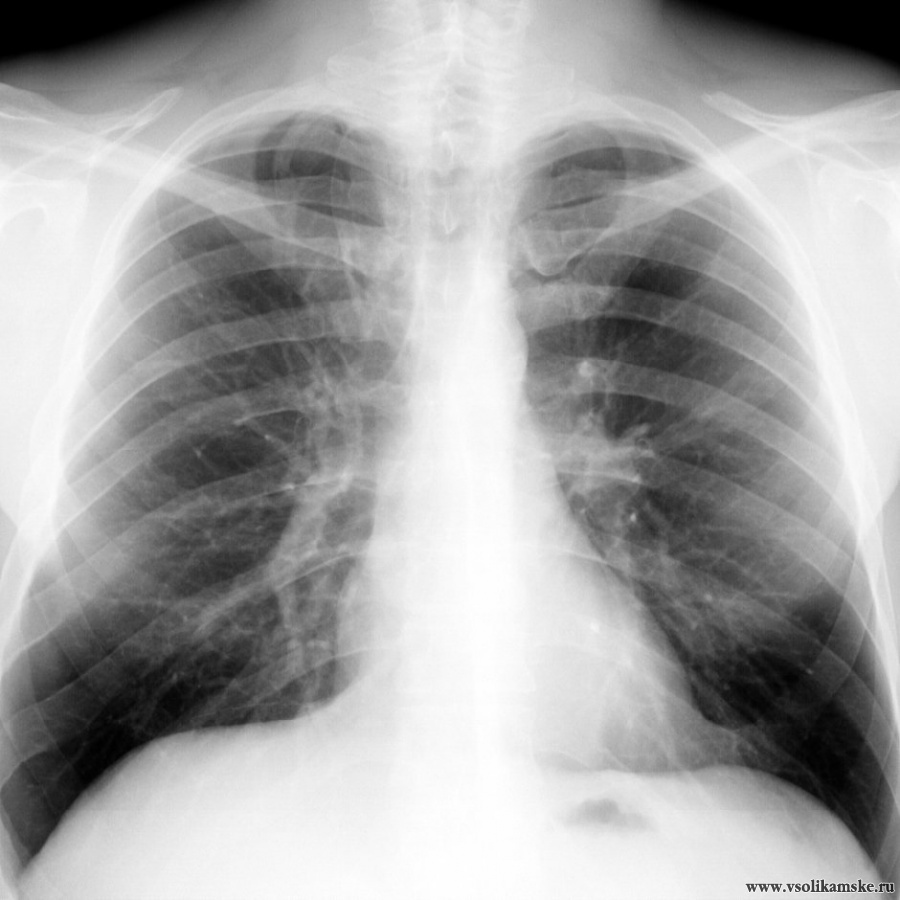

Нормальная рентгенограмма легких: что нужно знать

Раздел: Мудрость в объективе